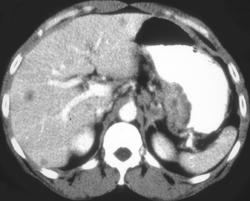

Polypoid Gastric Cancer